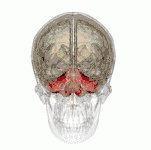

Cerebellum

Lesions are usually symmetrical in the periventricular region, diencephalon, the midbrain, hypothalamus, and cerebellar vermis. Brainstem lesions may include cranial nerve III, IV, VI and VIII nuclei, the medial thalamic nuclei, and the dorsal nucleus of the vagus nerve. Oedema may be found in the regions surrounding the third ventricle, and fourth ventricle, also appearing petechiae and small hemorrhages.[52] Chronic cases can present the atrophy of the mammillary bodies.[53]

Endothelial proliferation, hyperplasia of capillaries, demyelination and neuronal loss can also occur.